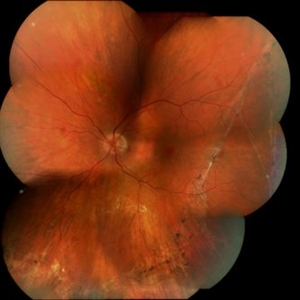

Optic Atrophy and Attenuated Retinal Vessels Following Endophthalmitis

This elderly lady underwent a vitrectomy for post-surgical endophthalmitis. The infection was successfully treated but the functional outcome was poor because of optic atrophy and attenuated retinal vessels.

Photographer: Alex Fraser

Imaging device: Optos Camera

Condition/keywords: attenuated vessels, endophthalmitis, optic atrophy, post-vitrectomy